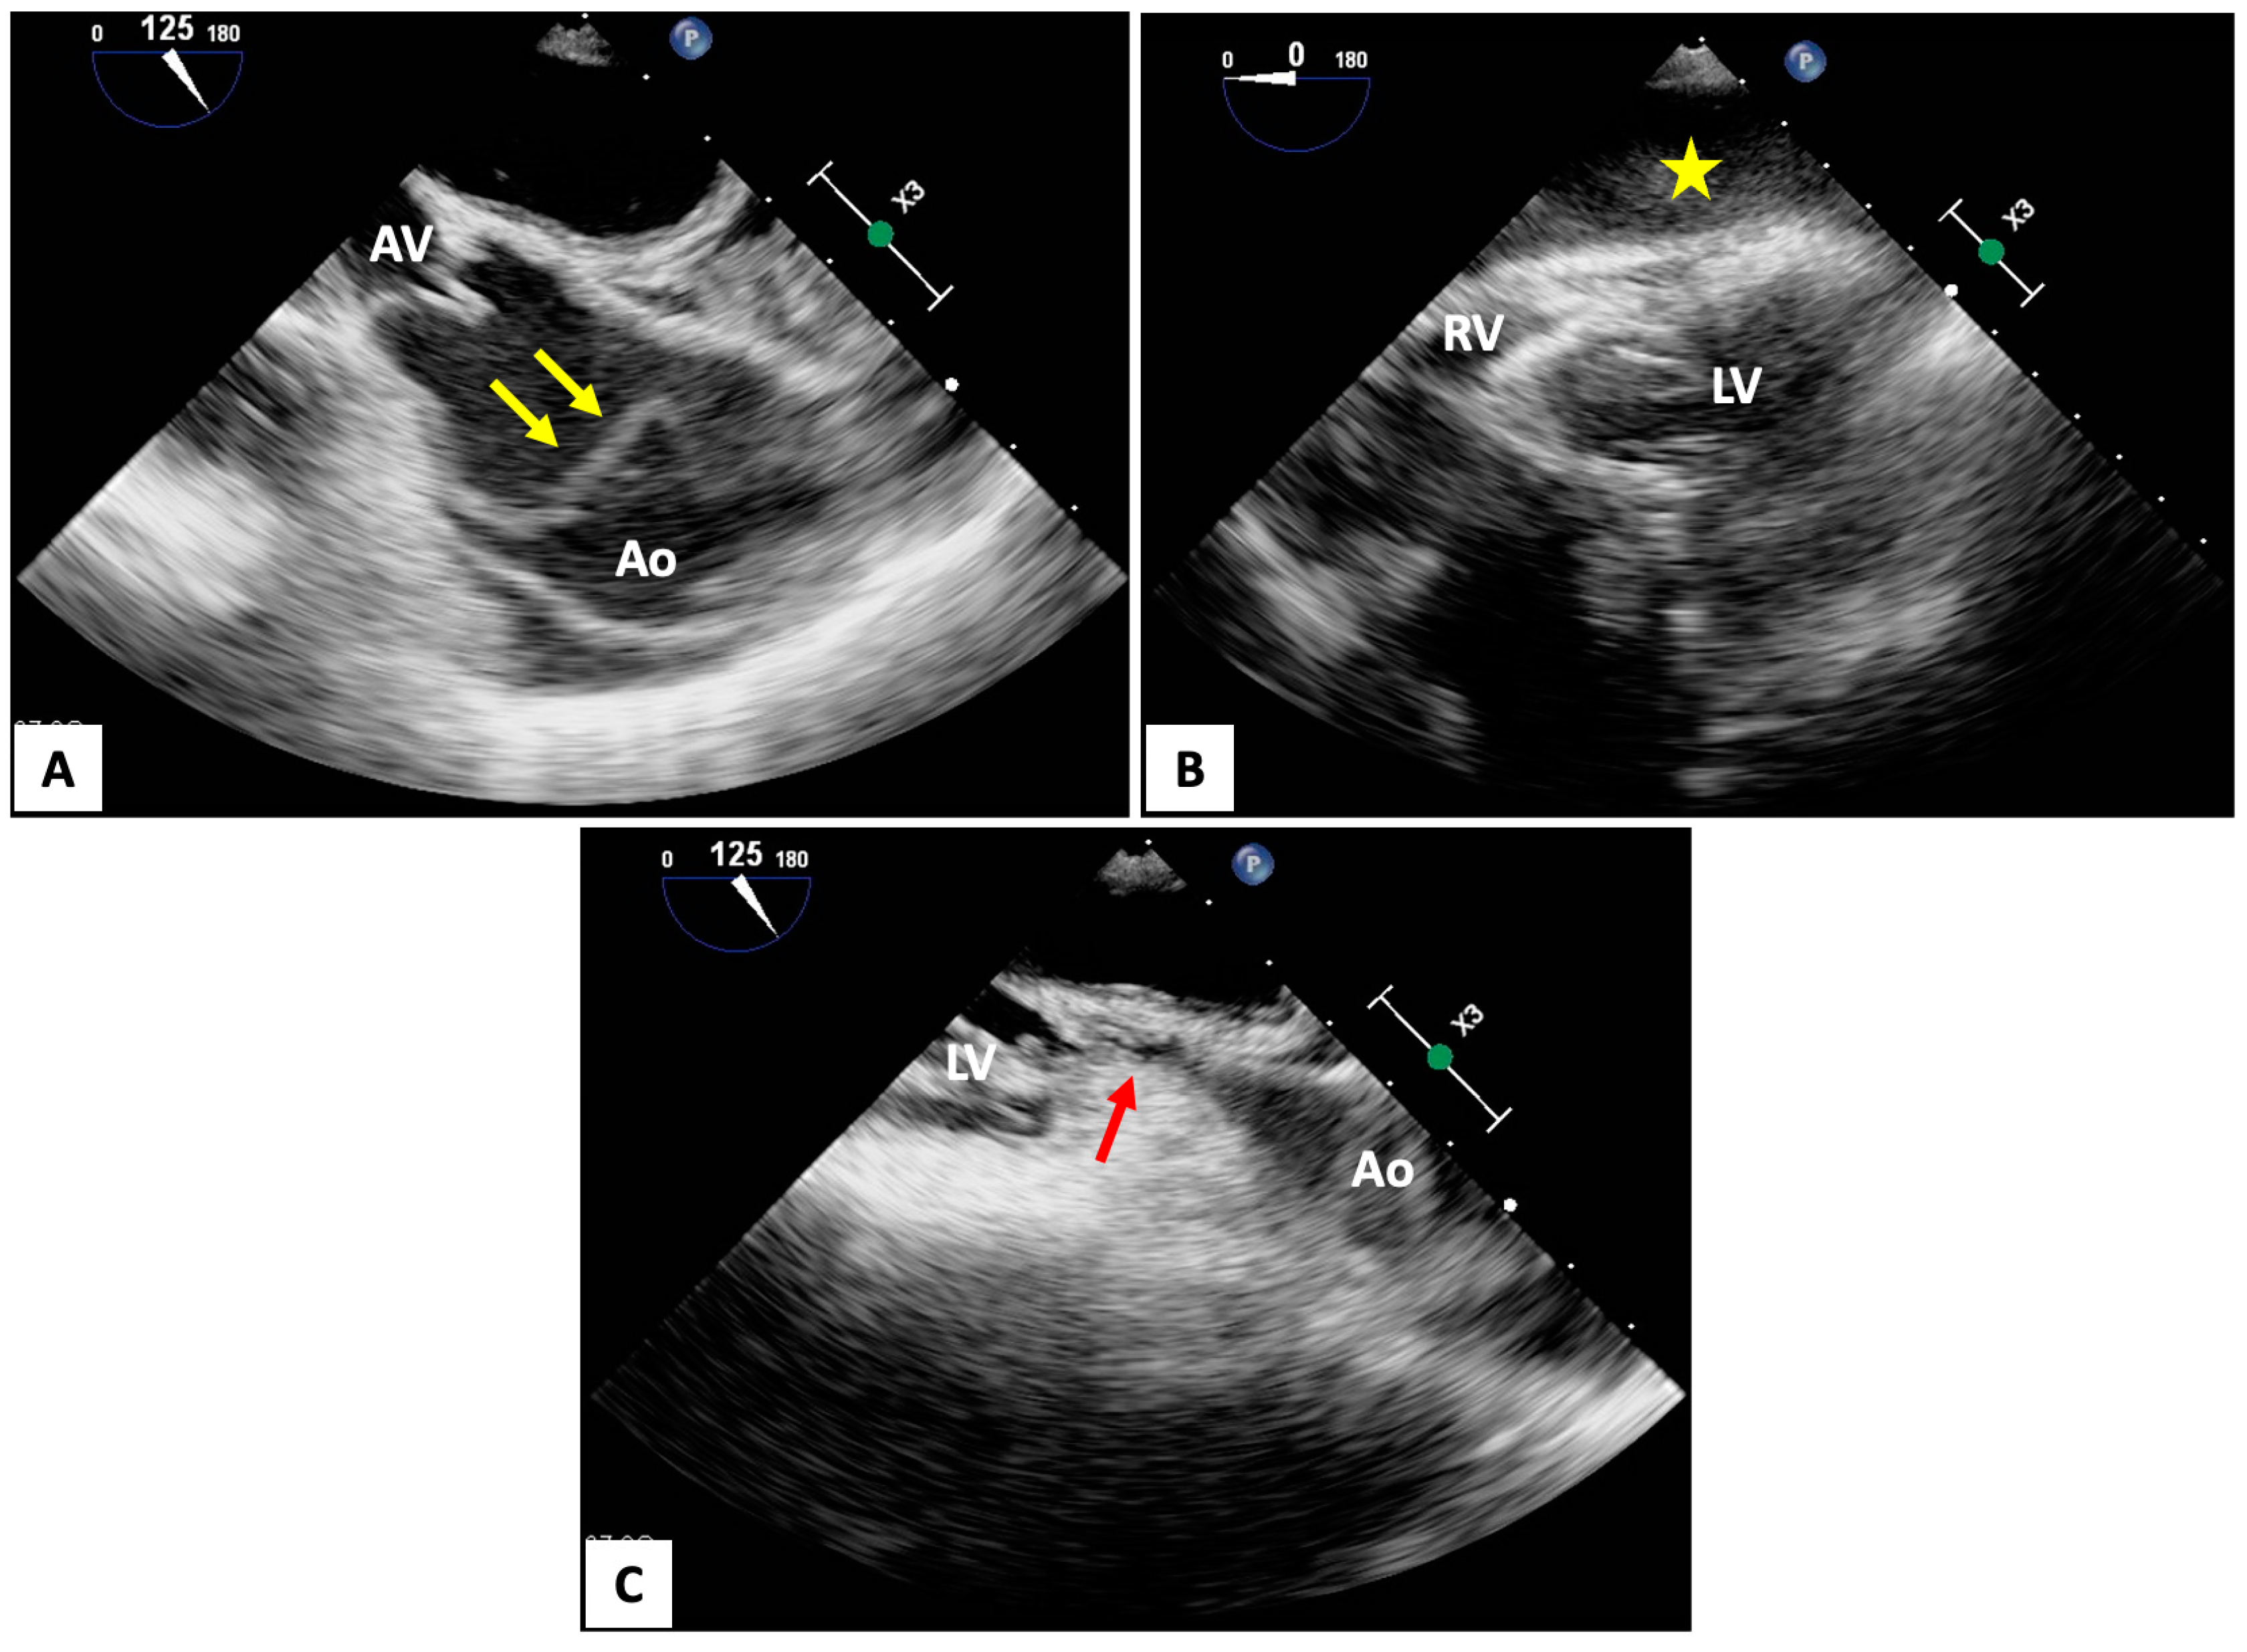

4.2. Transesophageal Echocardiography (TEE)

- Catena, E.; Ottolina, D.; Fossali, T.; Rech, R.; Borghi, B.; Perotti, A.; Ballone, E.; Bergomi, P.; Corona, A.; Castelli, A.; et al. Association between left ventricular outflow tract opening and successful resuscitation after cardiac arrest. Resuscitation 2019, 138, 8–14. [Google Scholar] [CrossRef] [PubMed]

- Teran, F.; Prats, M.I.; Nelson, B.P.; Kessler, R.; Blaivas, M.; Peberdy, M.A.; Shillcutt, S.K.; Arntfield, R.T.; Bahner, D. Focused Transesophageal Echocardiography During Cardiac Arrest Resuscitation: JACC Review Topic of the Week. J. Am. Coll. Cardiol. 2020, 76, 745–754. [Google Scholar] [CrossRef] [PubMed]

- Nestaas, S.; Stensaeth, K.H.; Rosseland, V.; Kramer-Johansen, J. Radiological assessment of chest compression point and achievable compression depth in cardiac patients. Scand. J. Trauma. Resusc. Emerg. Med. 2016, 24, 54. [Google Scholar] [CrossRef] [PubMed]

- Shin, J.; Rhee, J.E.; Kim, K. Is the inter-nipple line the correct hand position for effective chest compression in adult cardiopulmonary resuscitation? Resuscitation 2007, 75, 305–310. [Google Scholar] [CrossRef] [PubMed]

- Hwang, S.O.; Zhao, P.G.; Choi, H.J.; Park, K.H.; Cha, K.C.; Park, S.M.; Kim, S.C.; Kim, H.; Lee, K.H. Compression of the left ventricular outflow tract during cardiopulmonary resuscitation. Acad. Emerg. Med. 2009, 16, 928–933. [Google Scholar] [CrossRef] [PubMed]

- Anderson, K.L.; Fiala, K.C.; Castaneda, M.G.; Boudreau, S.M.; Arana, A.A.; Bebarta, V.S. Left ventricular compressions improve return of spontaneous circulation and hemodynamics in a swine model of traumatic cardiopulmonary arrest. J. Trauma. Acute Care Surg. 2018, 85, 303–310. [Google Scholar] [CrossRef] [PubMed]

- Marshall, R.A.; Morton, J.S.; Luchkanych, A.M.S.; El Karsh, Y.; El Karsh, Z.; Morse, C.; Tomczak, C.R.; Grunau, B.E.; Olver, T.D. Left ventricle chest compression improves ETCO2, blood pressure, and cerebral blood velocity in a swine model of cardiac arrest and cardiopulmonary resuscitation. Resusc. Plus 2022, 12, 100326. [Google Scholar] [CrossRef] [PubMed]

- Teran, F.; Owyang, C.G.; Martin-Flores, M.; Lao, D.; King, A.; Palasz, J.; Araos, J.D. Hemodynamic impact of chest compression location during cardiopulmonary resuscitation guided by transesophageal echocardiography. Crit. Care 2023, 27, 319. [Google Scholar] [CrossRef]